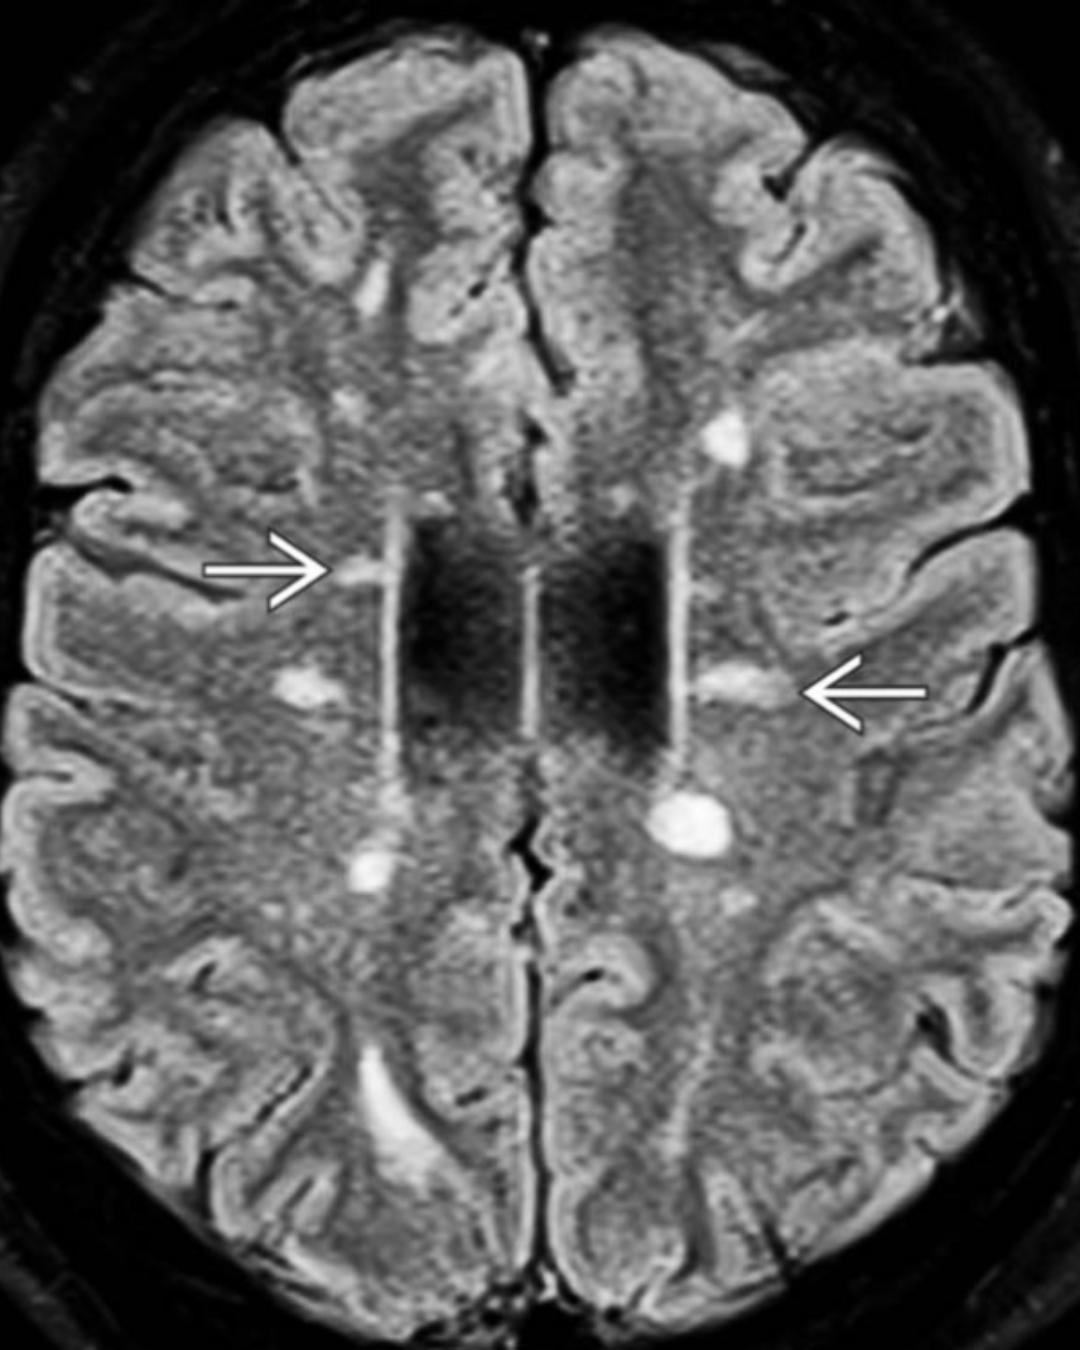

Achados típicos RM Esclerose Múltipla (EM)

lesões adjacentes ao ventrículo lateral

dedos de Dawson → lesões ovoides perpendiculares ao ventrículo lateral

lesões sucorticais em U